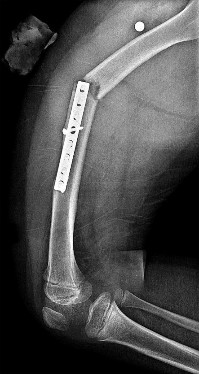

Question 32

An 8-year-old, 35 kg boy sustains a transverse midshaft fracture of the right femur. He is treated with titanium elastic nails (TENs). What is the most common complication associated with this surgical treatment?